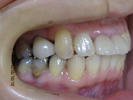

50代女性

![]() |

治療前 |

||

治療中。仮歯。 左上の奥にインプラント埋入。 噛みあわせ治療を行いました |

治療後 全体の歯で食事がおいしくできるようになったと喜んでおられました。 |